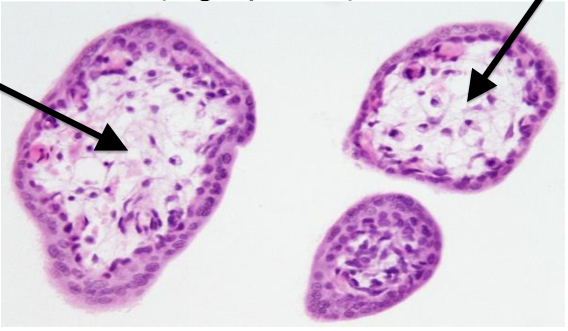

What tissue is this?

Parathyroid gland

42

What tissue is this?

Adrenal gland

43

What tissue is this?

Adrenal gland - cortex

44

What tissue is this?

Adrenal gland - medulla